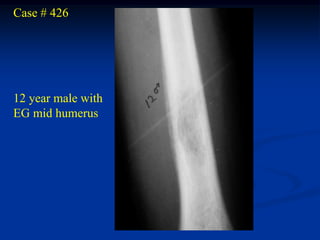

Case # 426

12 year male with

EG mid humerus

Arteriogram

Bone Scan